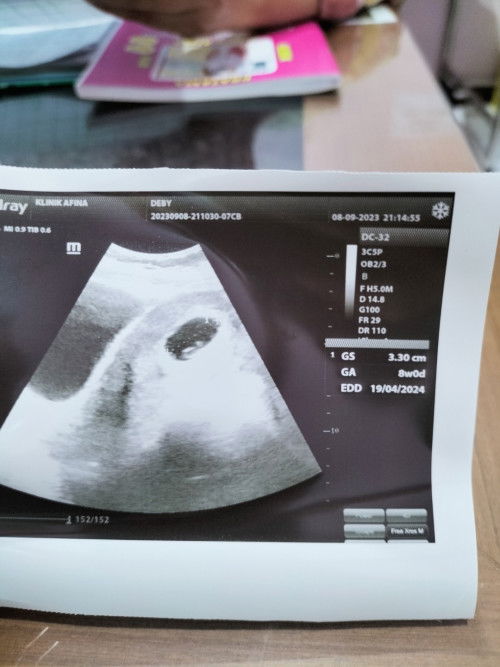

Hamil 8w soal djj

Bunda , kmren aku ada sedikit flek , mlmnya langsung priksa ke klinik . Pas usg sudah ada kanton dan janin nya , djj nya bun sangat lembut bun ga telalu kedengeran . Dan aku baru sadar klo di fto usg crl nya g di ukur 🥹 Menurut bunda klo usia 8w djjnya ga telalu kedengeran itu normal ga bun?